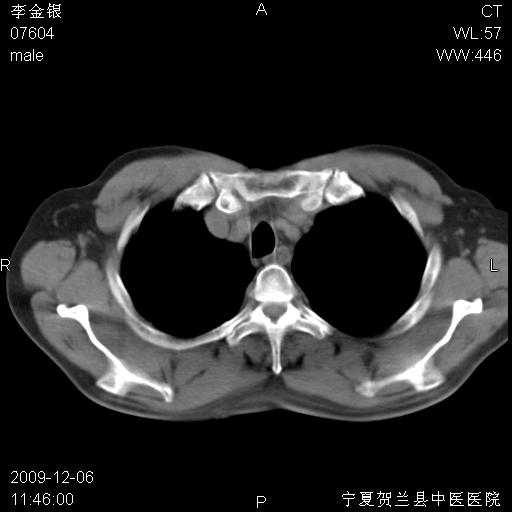

该病人 ,男,62岁,主因咳痰带血两天

支气管壁明显增厚 管腔狭窄,腔静脉后多个淋巴肿大,结合年龄病史考虑右肺上叶中央型肺癌并阻塞性肺炎

右肺上叶后段支气管阻塞,右上肺门占位,相应肺段阻塞性肺炎,右肺门有淋巴结肿大。诊断右肺上叶中心型肺癌,阻塞性肺肺炎、右肺门淋巴结转移。

符合中央型肺癌的ct表现并肺出血。但有一点腔静脉后有一钙化的淋巴结啊